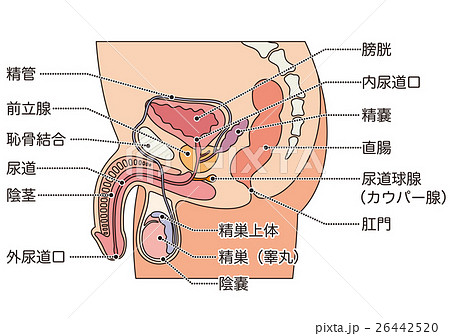

男性生殖器 断面図のイラスト素材

男性生殖器 断面図のイラスト素材

男性生殖器断面人体図 名称付き メディカルイラスト図鑑 無料の医療 美容素材集

男性生殖器 断面図のイラスト素材

男性生殖器 断面図のイラスト素材